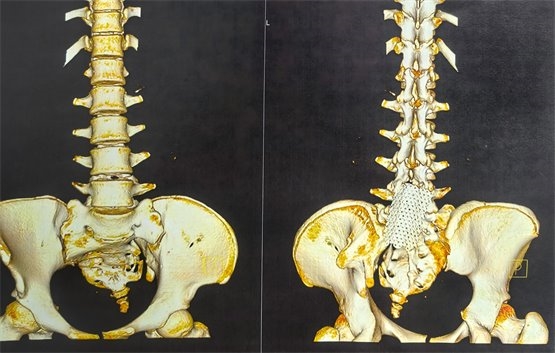

图3为此次骶神经电刺激穿刺前骶椎CT三维成像,可见骶椎裂,且骶椎扭转畸形,根据片子可见,手术穿刺风险及难度明显增大